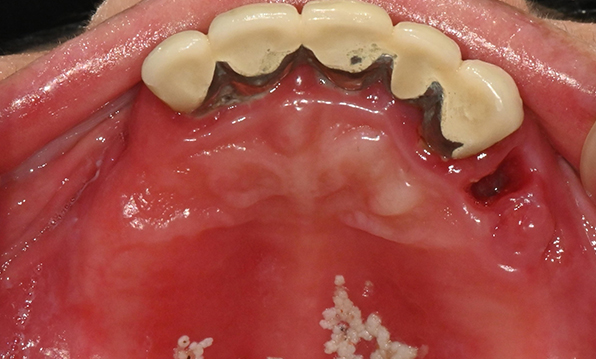

잇몸뼈가 얇은 상태

-

잇몸뼈 충분히 이식 후 임플란트 식립

성공을 위한 노하우, 잇몸뼈 재건 기술

전체 임플란트를 해야하는 환자들은

대부분 고령의 환자들로 오랜 틀니 사용

또는 노화로 인해 치조골이

거의 남아있지 않는 경우가 많습니다.

이 때, 치조골 이식을 병행하여 잇몸뼈 재건 후 안정적인 임플란트 식립을 하고 있습니다.

치료기간 : 2021.04.12~2021.09.15